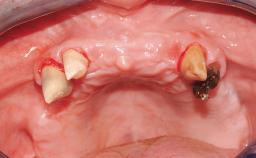

Immediate Loading of Six Implants in the Maxilla and Final Restoration with a Full-Arch CAD/CAM Zirconia FDP

A 63-year-old male patient was referred for a consultation and treatment of partial edentulism in the maxilla. The patient presented with residual anterior teeth and declined a partial removable prosthesis. He reported that the maxillary posterior teeth had been extracted due to mobility and periodontal disease two months before the consultation. The patient’s chief complaint was that his residual maxillary teeth were mobile and that he was unable to chew. The patient’s desire was a stable and comfortable fixed maxillary rehabilitation. The patient was a light smoker (fewer than 10 cigarettes/ day), and his medical history was without significant findings. He was not on any regular medication at the time of consultation. The extraoral examination revealed a normal physiognomy with a correct distribution of the facial thirds. The patient presented a low lip line, and the transition line between teeth and soft tissues was not exposed during a forced smile.

Bone Augmentation Horizontal|Simultaneous

Bone Volume Horizontally and vertically sufficient Horizontally deficient Deficient vertically or deficient vertically AND horizontally